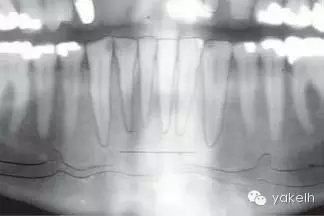

¤¤與口腔頜面部的其他供區(qū)相比,頦部術(shù)后并發(fā)癥的發(fā)生率更高。當(dāng)骨塊以及環(huán)形骨塊移除后,下前牙感覺異常是術(shù)后常見并發(fā)癥。如切牙管神經(jīng)在取骨過程中受損(圖13.24,圖13.25),患者會(huì)感到切牙感覺異常,該損傷通常在6個(gè)月內(nèi)可以自行修復(fù),此時(shí)前牙通常不需要做根管治療。但也會(huì)發(fā)生由于牙髓受損,導(dǎo)致下切牙變色或者繼發(fā)性牙本質(zhì)形成(圖13.26)。即使于前庭溝處做切口,也可出現(xiàn)頦部神經(jīng)感覺異常。骨移植患者發(fā)生頦神經(jīng)感覺異常的幾率較低,但是也有高達(dá)43%的并發(fā)癥發(fā)生率報(bào)道(13.27)。在寒冷的天氣時(shí),頦部氣候功能癥也有報(bào)道。盡管大多數(shù)受損的患者可恢復(fù)正常,但是仍給患者造成困擾。術(shù)前討論可能的并發(fā)癥是明智的,這包括手術(shù)會(huì)導(dǎo)致牙齒以及頦部感覺的異常。盡管未有術(shù)后頦部軟組織外形改變的報(bào)道,但患者往往擔(dān)心該區(qū)域取骨后是否會(huì)影響美觀。影像學(xué)證據(jù)表明,在一些老年患者中,供區(qū)骨空腔不能完全修復(fù)。用可吸收的骨替代品,如骨庫骨或者小牛骨充填供區(qū)的缺損,可以減少患者的疑慮。術(shù)后沒有發(fā)生過頦部下垂,但為防止頦部下垂,在取骨時(shí)應(yīng)避免把下頜骨上的組織完全撕脫。曾有報(bào)道在取骨后,下頜骨剩余舌側(cè)骨板發(fā)生骨折。如前所述,這可能是取骨時(shí),太靠近下頜骨邊緣所造成的。頦部取骨的術(shù)后疼痛比較明顯。術(shù)后應(yīng)用長(zhǎng)效局麻藥,如布比卡因行下頜神經(jīng)阻滯麻醉,可以延遲疼痛的發(fā)生,以便人體有充分的時(shí)間來吸收止痛藥。術(shù)前應(yīng)用非甾體類藥物,如布洛芬等可減少疼痛和腫脹。

圖13.24 全景片提示切牙管的位置。

圖13.25 在頦部取骨過程中,經(jīng)常損傷到下齒槽神經(jīng)的切牙分支。